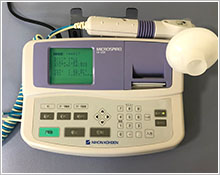

呼吸機能測定器

喘息などの閉塞性肺障害、肺活量などを調べます。